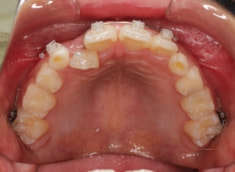

治療法:拡大プレート+フルパッシブブラケット(クリアスナップ)

治療中